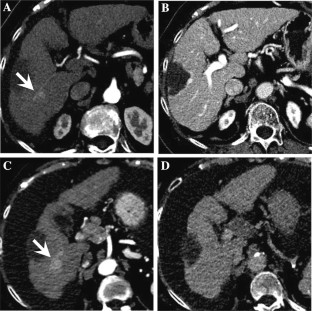

Fig. 1